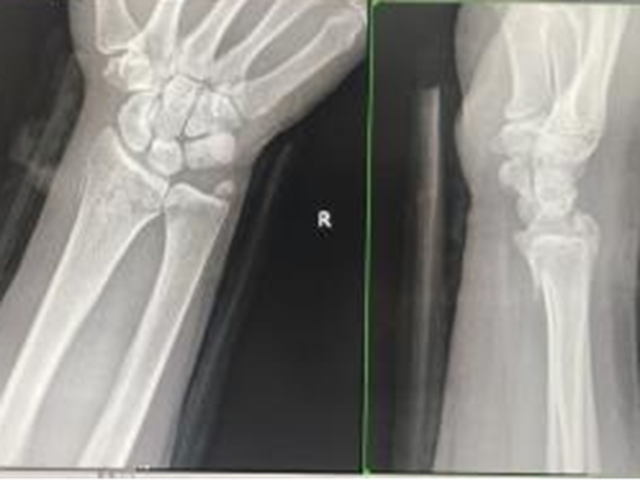

复位后复查

“擒拿扶正、拔伸牵引、推端提按、抱迫靠拢、屈伸对合”,一整套手法下来不到5分钟骨折整复完毕,外敷秘制中药,再小夹板固定,最后配合理筋手法,梁女士瞬间觉得骨折处没那么痛,手指活动也明显灵活了。